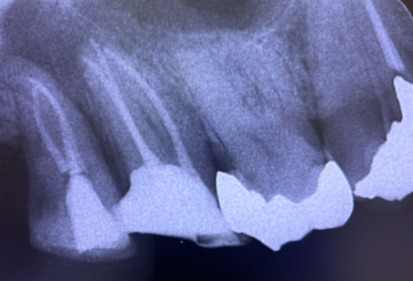

虫歯が進行すると、歯の神経(歯髄)にまで感染が広がります。この段階では、感染した神経を取り除き、根管(神経が通る管)を丁寧に清掃してから被せ物を施す治療が必要です。「根管内を徹底的に清掃する作業」は非常に難しく、慎重な処置が求められます。根管は複雑に分岐しており、清掃が不十分だと「痛み」や「腫れ」などの症状を引き起こし、最終的に「根尖病巣」と呼ばれる病気に繋がることもあります。下の画像の「黒い部分」は、神経が入っている根管であり、この部分をすべてしっかりと清掃しなければなりません。